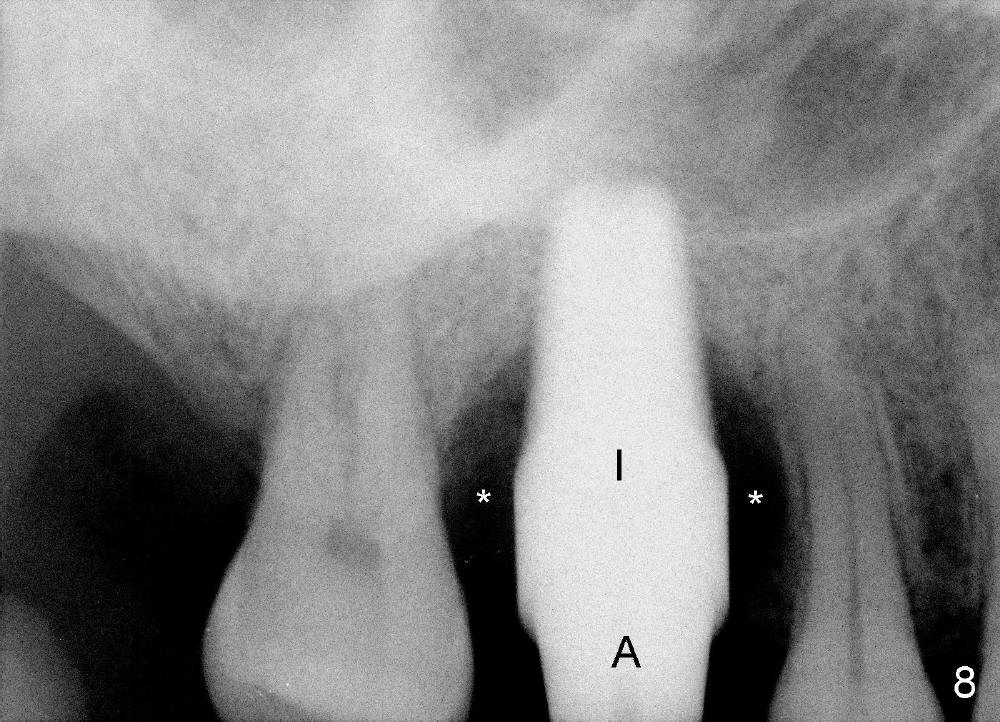

The upper right 1st molar of a 48-year-old man has severe perio endo disease (Fig.1 #3); the bone height for immediate implant (Fig.2) is about 3.5 mm (Fig.1 vertical line). There is a buccal (Fig.3 B) abscess (*); the palatal (Fig.4 P) root is exposed. After extraction, the socket available for immediate implant (Fig.5,6 S) is buccal (without septum), whereas the apex of the palatal root is far away from the main socket. In fact there is an advantage: the socket is smaller. Osteotomy is created in the main socket as palatal as possible, using osteotomes, reamers and taps (Fig.7 T). The sinus floor is lifted (Fig.7 ^). When 7x17 mm implant is placed (Fig.8 I), the insertion torque is >60 Ncm. The remaining socket (Fig.8 *) is to be packed with mixture of autogenous bone, allograft and synthetic bone (Osteogen) (Fig.9,10 <). Immediate insertion of an abutment (Fig.8-10 A) helps retain perio dressing (Fig.11,12). No collagen membrane is used in this case to cover the bone graft before placement of perio dressing. Postop the patient cannot tolerate oral Amoxicillin because of stomach upset. The dose is reduced. Two weeks postop, the perio dressing is stable, but discolors (Fig.13). When the dressing is removed, the buccal bone graft is exposed, which is not abnormal. What is unusual is discoloration (Fig.14). The significance of the latter is not revealed until 3 months postop when the patient remains asymptomatic, but there is an apical fistula (Fig.15 <). There is a communication between the fistula and the buccal sulcus of the implant: water passing freely. Based on the position of the buccal plate of the neighboring teeth (*), the buccal plate of the implant should be lost, which is consistent with finding of PA (Fig.16, as compared to Fig.8). Guided bone regeneration seems necessary.